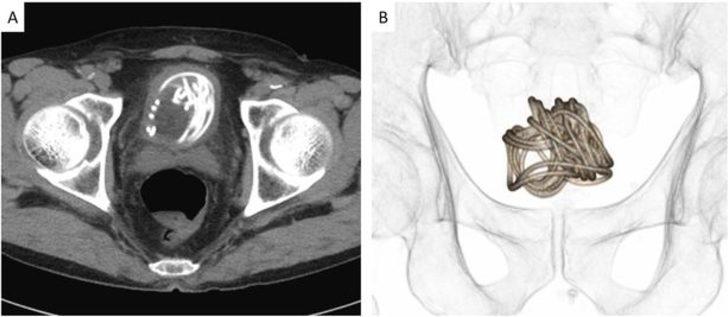

İp mesanenin içinde düğümlendiği için sağlık görevlileri cerrahi işleme ihtiyaç duydu. Urology Case Reports'ta yayınlanan çalışmanın baş yazarı Profesör Toshiki Kijima, taramaların ve modellerin, dolaşıklık nedeniyle ipi penisten geri çekme şansının imkansız olduğunu kanıtladığını söyledi.

Profesör Kijima prosedüre dair olarak, "İpin uzunluğu ve mesaneye dolanması düşünüldüğünde transüretral ekstraksiyon zordu. Geleneksel olarak, yabancı cisimleri çıkarmak için kavrama forsepsleri ve geri alma sepetleri kullanılır. Ancak, mesaneye yerleştirilen teller genellikle mesane kasıldıkça kıvrılır; bu nedenle, tel benzeri yabancı cisimler için özel dikkat gereklidir.” ifadeleri kullanıldı.